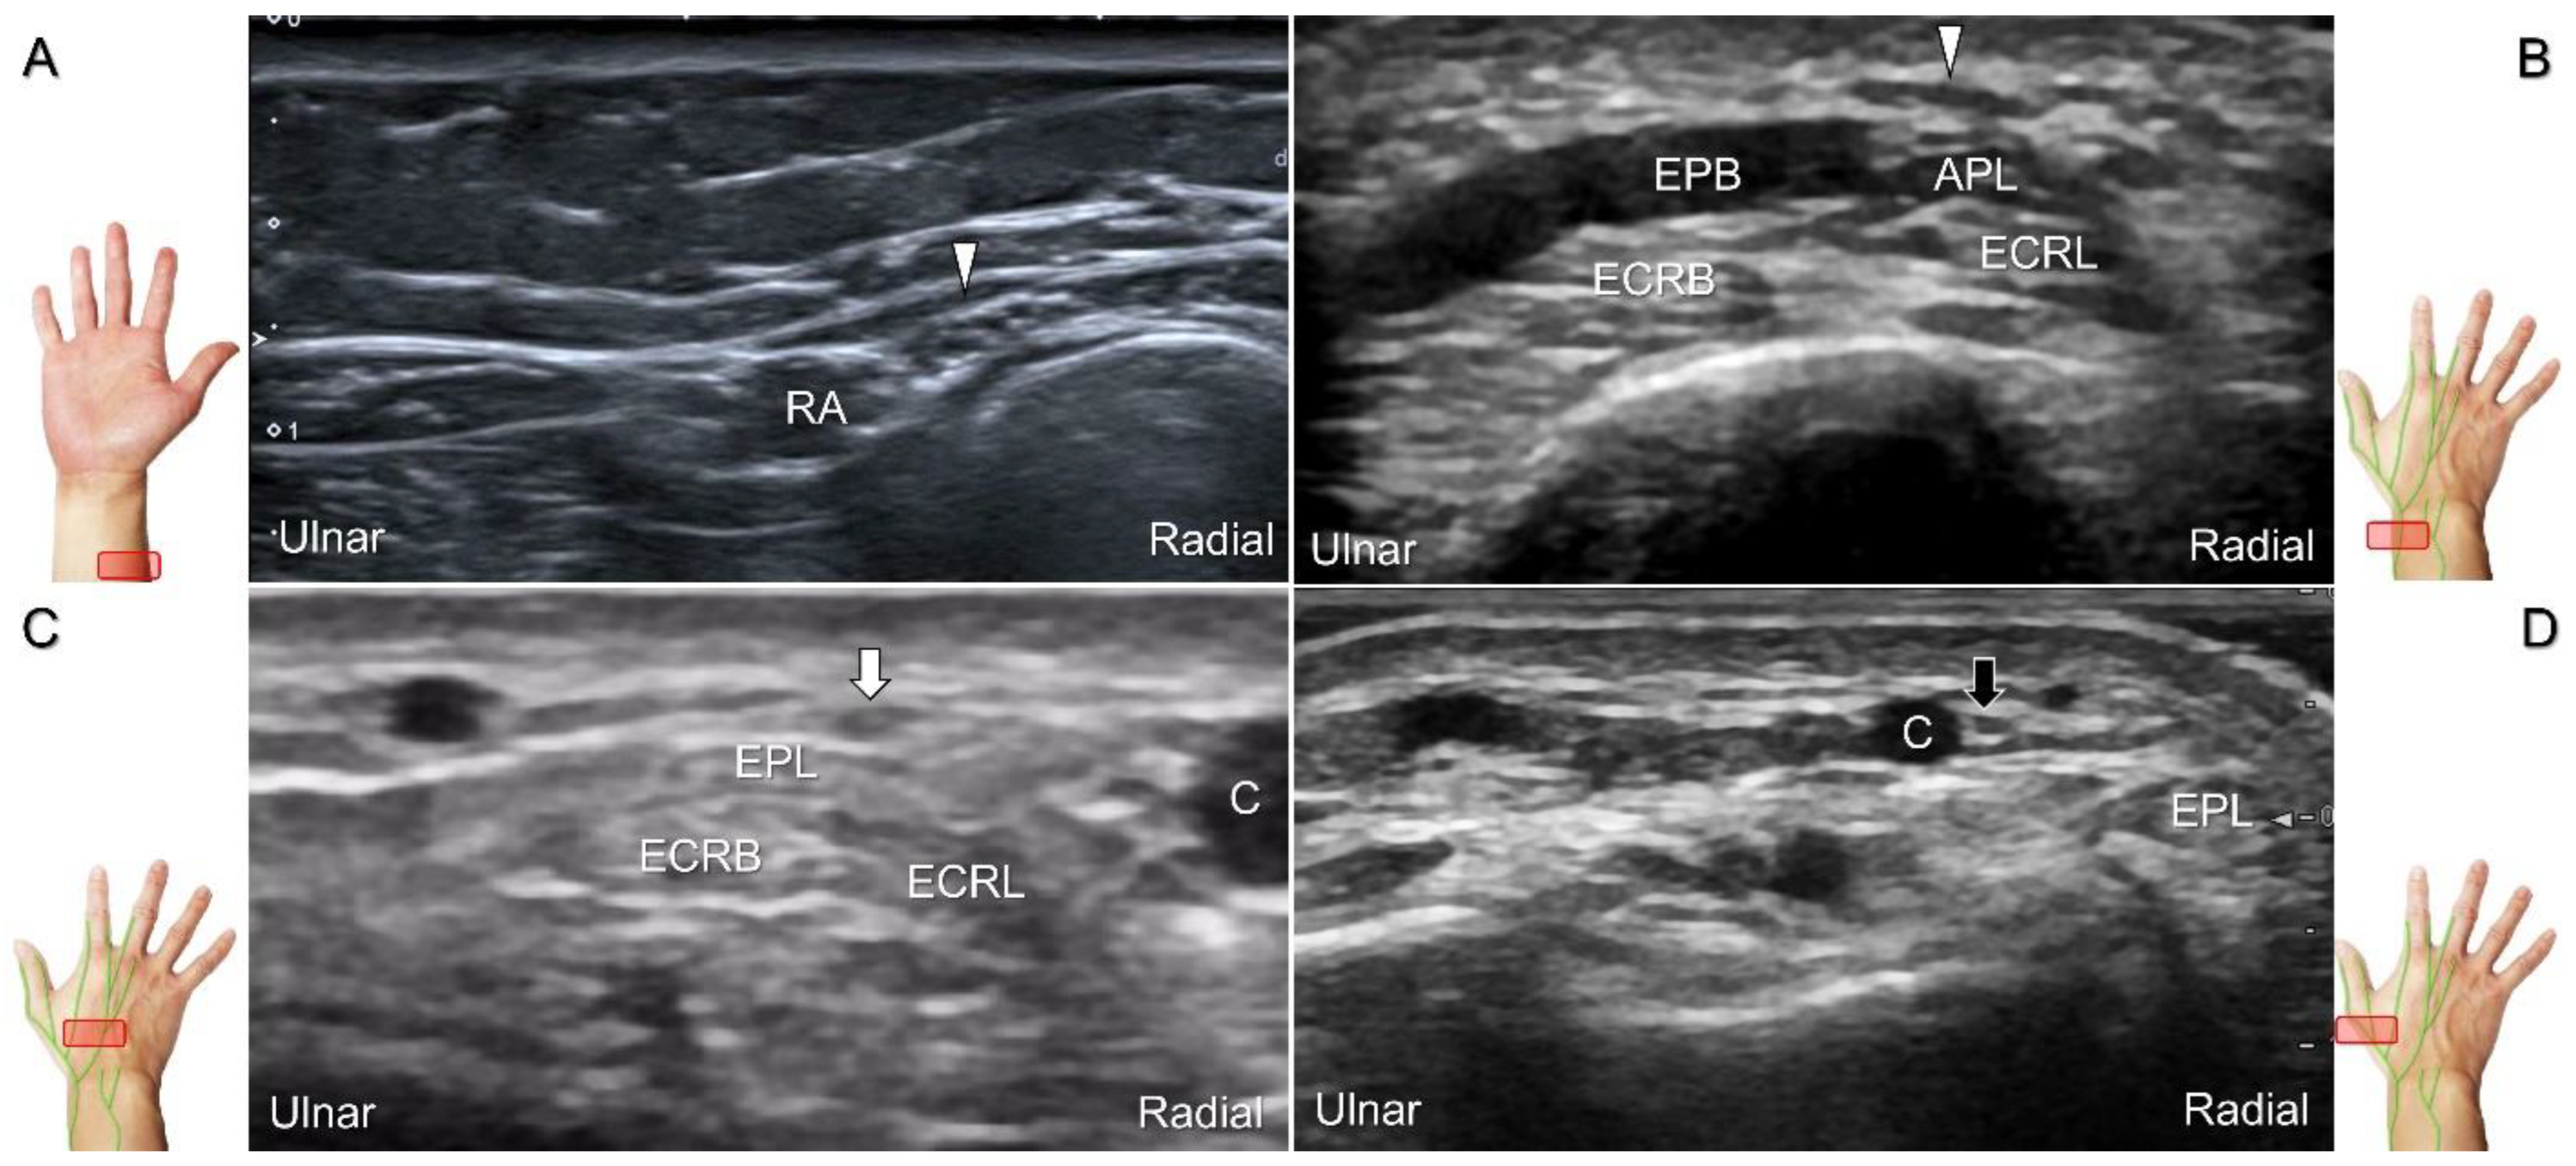

Scanning Technique

With the forearm supinated, the transducer is positioned in the axial plane at the lateral aspect of the antecubital fossa. The superficial and deep radial nerves are situated between the brachioradialis and brachialis muscles. The superficial radial nerve initially courses next to the radial artery below the brachioradialis muscle, and then departs from the radial artery in the distal third of the forearm (Figure 21A). Distally, it pierces the antebrachial fascia between the extensor carpi radialis longus and brachioradialis tendons. When tracking the terminal portion of the superficial radial nerve, the forearm can be pronated, as it courses toward the dorsal radial aspect of the wrist/hand. The superficial radial nerve travels above the proximal intersection junction between the first and second dorsal extensor compartments (Figure 21B). Later, it divides into the dorsomedial and dorsolateral branches. The former courses above the distal intersection junction of the second and third compartments (Figure 21C). The latter runs beside the extensor pollicis longus tendon (Figure 21D).

Figure 21. Sonographic imaging (short-axis view) of the superficial radial nerve from the distal third of the supinated forearm (A). With the pronated forearm, the nerve is seen to travel above the proximal intersection junction (B), divide into the dorsomedial branch coursing above the distal intersection junction (C), and the dorsolateral branch running beside the extensor pollicis longus tendon (D). Arrowheads: superficial radial nerve; white arrow: dorsomedial branch; black arrow: dorsolateral branch. RA: radial artery; APL: abductor pollicis longus tendon; EPB: extensor pollicis brevis tendon; ECRL: extensor carpi radialis longus tendon; ECRB: extensor carpi radialis brevis tendon; EPL: extensor pollicis longus tendon; C: cephalic vein.